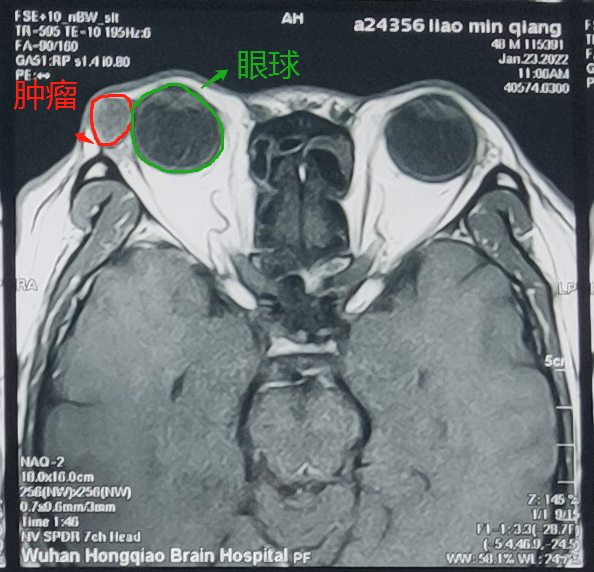

廖先生这才来到武汉艾格眼科医院,泪道眼眶肿瘤科程勉征检查发现,这个包是泪腺肿瘤,泪腺肿瘤是常见的眼眶肿瘤,约占眼眶内肿瘤的 20%~23%。泪腺肿瘤的早期诊断及早期治疗非常重要。早期患者并不会有明显的不适感,所以大家很容易忽视。

1 月 25 日,廖先生在程勉征主任的建议下,接受了肿瘤切除手术,切下来的肿瘤 15 mm*10 mm*10 mm,后期通过病理切片检查,廖先生的肿瘤是良性的。这个结果让他心里的大石头终于落地。